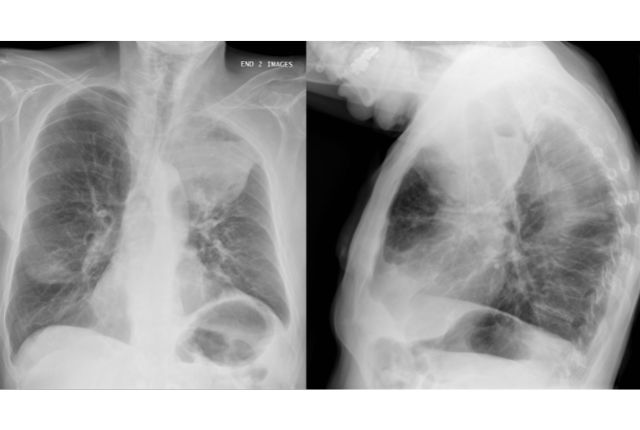

Le thorax se déforme et son diamètre avant-arrière augmente fortement. Les radiographies montrent un tissu pulmonaire qui perd peu à peu en surface.

Plusieurs examens sont nécessaires pour diagnostiquer un emphysème, afin d’exclure toutes les autres maladies pulmonaires. Scanners et radiographies permettent d’évaluer l’état des poumons et la distension du thorax. Pour connaître le taux d’oxygène dans le sang, une saturométrie est généralement effectuée, et consiste en la pose d’un petit appareil sur un doigt. En complément, une prise de sang est nécessaire pour connaître le taux de gaz carboniques dans le sang. La ponction doit se faire dans une artère, généralement au niveau du poignet.